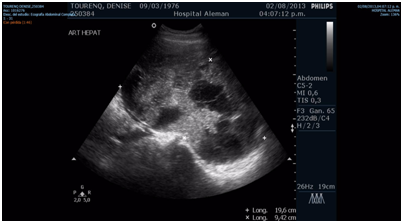

A 37-years-old patient started with non-specific abdominal pain in the year 2013 in an 8-week´s pregnancy context. She presented abdominal ultrasound evidencing: multiple isoecogenic nodules in the left lobe and in the right hepatic lobe with central necrobiosis. 9mm thickening of the hepatic angle of the colon and reduction of light of 8mm with ascending colon dilation. Video colonoscopy: progresses to rectum-sigma from where cannot progress longer. Hepatic lesions were punctured. Pathological anatomy reveals: malignant lesion compatible with primary colon tumor.